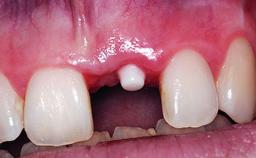

A 32-year-old female Caucasian patient with a compromised maxillary right central incisor was referred to us by a general dentist. Her chief complaints were discomfort and mobility of tooth 11 with unsatisfactory esthetics due to discoloration. The patient reported a previous trauma, some years earlier, as the origin of pathology on the afflicted tooth. Anamnesis was negative for any other dental or periodontal pathology in the remaining dentition. The patient did not take any medication and reported to be a light smoker (5–10 cigs/day). She had high esthetic expectations of her treatment. The extraoral examination revealed a high smile line with full exposure of her maxillary teeth and surrounding soft tissue in the area between the second premolars.

Placement Protocol Early or late implant placement

Loading Protocol Conventional or early